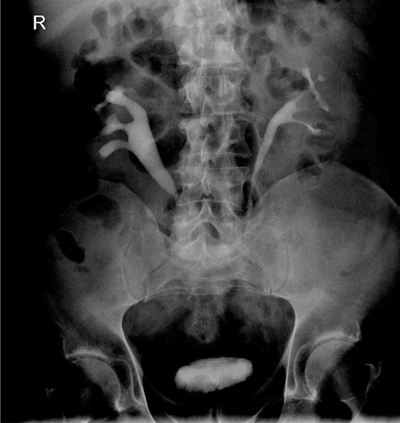

A 59-year-old man presented with right loin pain. His GP arranged for him to have an intravenous urogram (IVU) and subsequent CT urogram performed.

Retroperitoneal fibrosis. Proximal hydronephroureterosis, tapering of the ureteric lumen and medial deviation of the ureter.